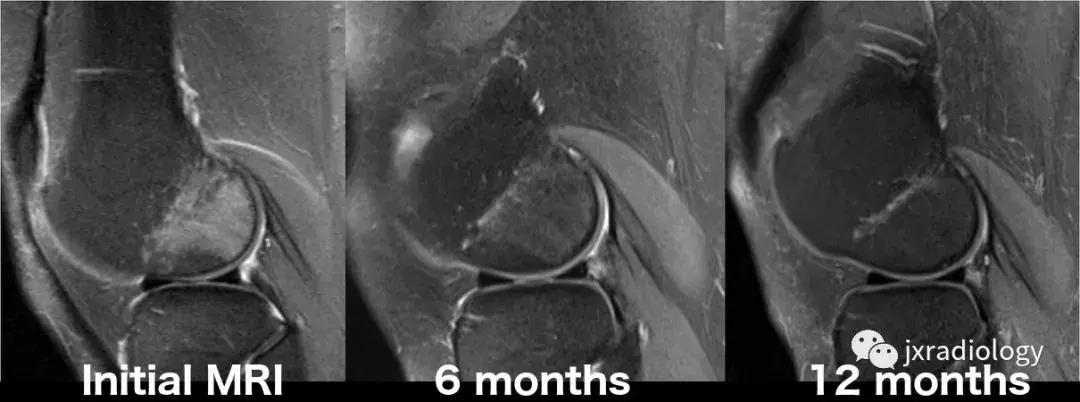

图25:短暂性骨髓水肿综合征(短暂性骨质疏松症):30岁女性急性膝部疼痛的矢状位FS-PDWI MR影像显示骨髓水肿,涉及非负重区域股骨外侧髁骨髓水肿在1年内几乎完全自发消退。短暂性骨髓水肿综合征是自限性病变,其表现为与MRI研究中的骨髓水肿证据相关的关节痛。其病因仍不确定。